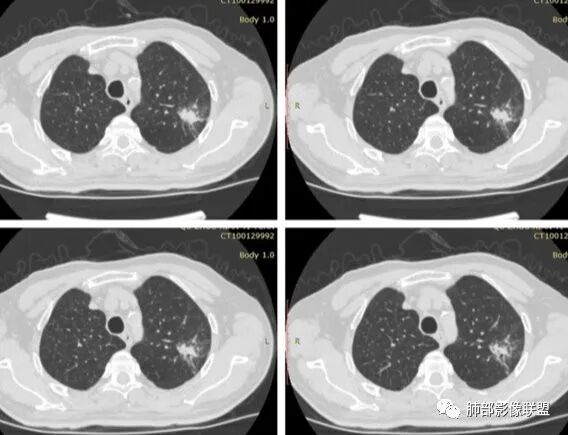

患者老年男性,体检发现左肺尖后段结节。吸烟史30年。胸部CT:左肺上叶尖后段胸膜下不规则实性结节,边缘欠清楚,边界欠光滑,可见长毛刺、分叶、胸膜粘连、平直征象,内可见支气管扩张、钙化及部分低密度坏死区,周围似见小卫星灶。综合考虑良性病变,结核可能大,鉴别恶性病变可能。

1、患者老年男性,无明显临床症状。

2、病灶位于左肺上叶尖后段,符合肺结核好发部位。

3、病灶密度不均,可见钙化点,未显示空洞或液化。边缘收缩,U型凹陷、桃尖征、细长毛刺以及较长棘状突起。宽基底与胸膜相连,邻近胸膜广泛性增厚(未见栽赃侵入)。可见卫星病灶,周围的磨玻璃影比较松散,炎性病变征象多,符合结核的CT表现。

4、部分区域膨隆,未见支气管截断,肺门纵隔未见肿大淋巴结等,恶性征象少。

5、结合其无临床症状、病灶形态、病灶位置及发病率,结核居多,最后诊断在大家意料之中。